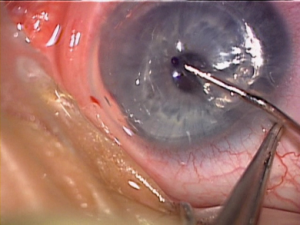

3) Implante de Lente Intraocular (LIO) Fácica no Tratamento do Ceratocone

As lentes intraoculares fácicas de câmara posterior são uma excelente alternativa de correção da visão de pacientes que não podem se beneficiar da cirurgia de implama laser. Elas são indicadas para pacientes que apresentem graus elevados de Miopia, Hipermetropia e Astigmastismo, ou Córneas muito curvas ou finas e em pacientes com Ceratocone – situações onde a cirurgia a laser não são recomendadas. Nesta modalidade de cirurgia, as lentes são implantadas e fixadas à íris (ex: lente de Artisan), na frente da íris (ex: lente Vivarte), ou atrás da íris (ex: lente ICL).

A Lente Artisan – feita de polimetilmetacrilato (PMMA), material inerte empregado para implantes em cirurgias intraoculares – é a lente ocular fácica mais comumente usada no mundo, com um longo histórico de sucesso. Essa lente pode ser usada para corrigir uma alta Miopia (de -5,0 D a -20,0 D) ou corrigir uma alta Hipermetropia (de +5,0 D a +10,0 D). A Lente Artisan tórica pode ser utilizada em graus elevados de astigmatismo, que necessitam de correção.

Vantagens das Lentes Artisan:

– A cirurgia pode ser realizada em paciente com córnea fina e córnea irregular;

– São potencialmente reversíveis;

– Permitem recuperação visual rápida;

– Preservam a acomodação (capacidade de enxergar para longe e perto) em pacientes jovens;

– Boa qualidade de correção da visão;

– Boa precisão de correção da visão.

Os riscos potenciais da cirurgia de implante de Lentes Fácicas, como em qualquer cirurgia intraocular, incluem a possibilidade de infecção e por essa razão é tratado um olho de cada vez, com um intervalo mínimo de 4 semanas entre os tratamentos. Há também raros casos descritos de possibilidade de dano à estrutura interna do olho, o que poderia levar ao Glaucoma, inflamação da íris (uveíte), complicações da retina, Descompensação da córnea ou a formação de uma Catarata precoce. Nesses casos, a Lente Artisan deverá ser removida.

Por essas razões, aconselhamos aos pacientes que cumpram o compromisso de revisões pós-operatórias em longo prazo.